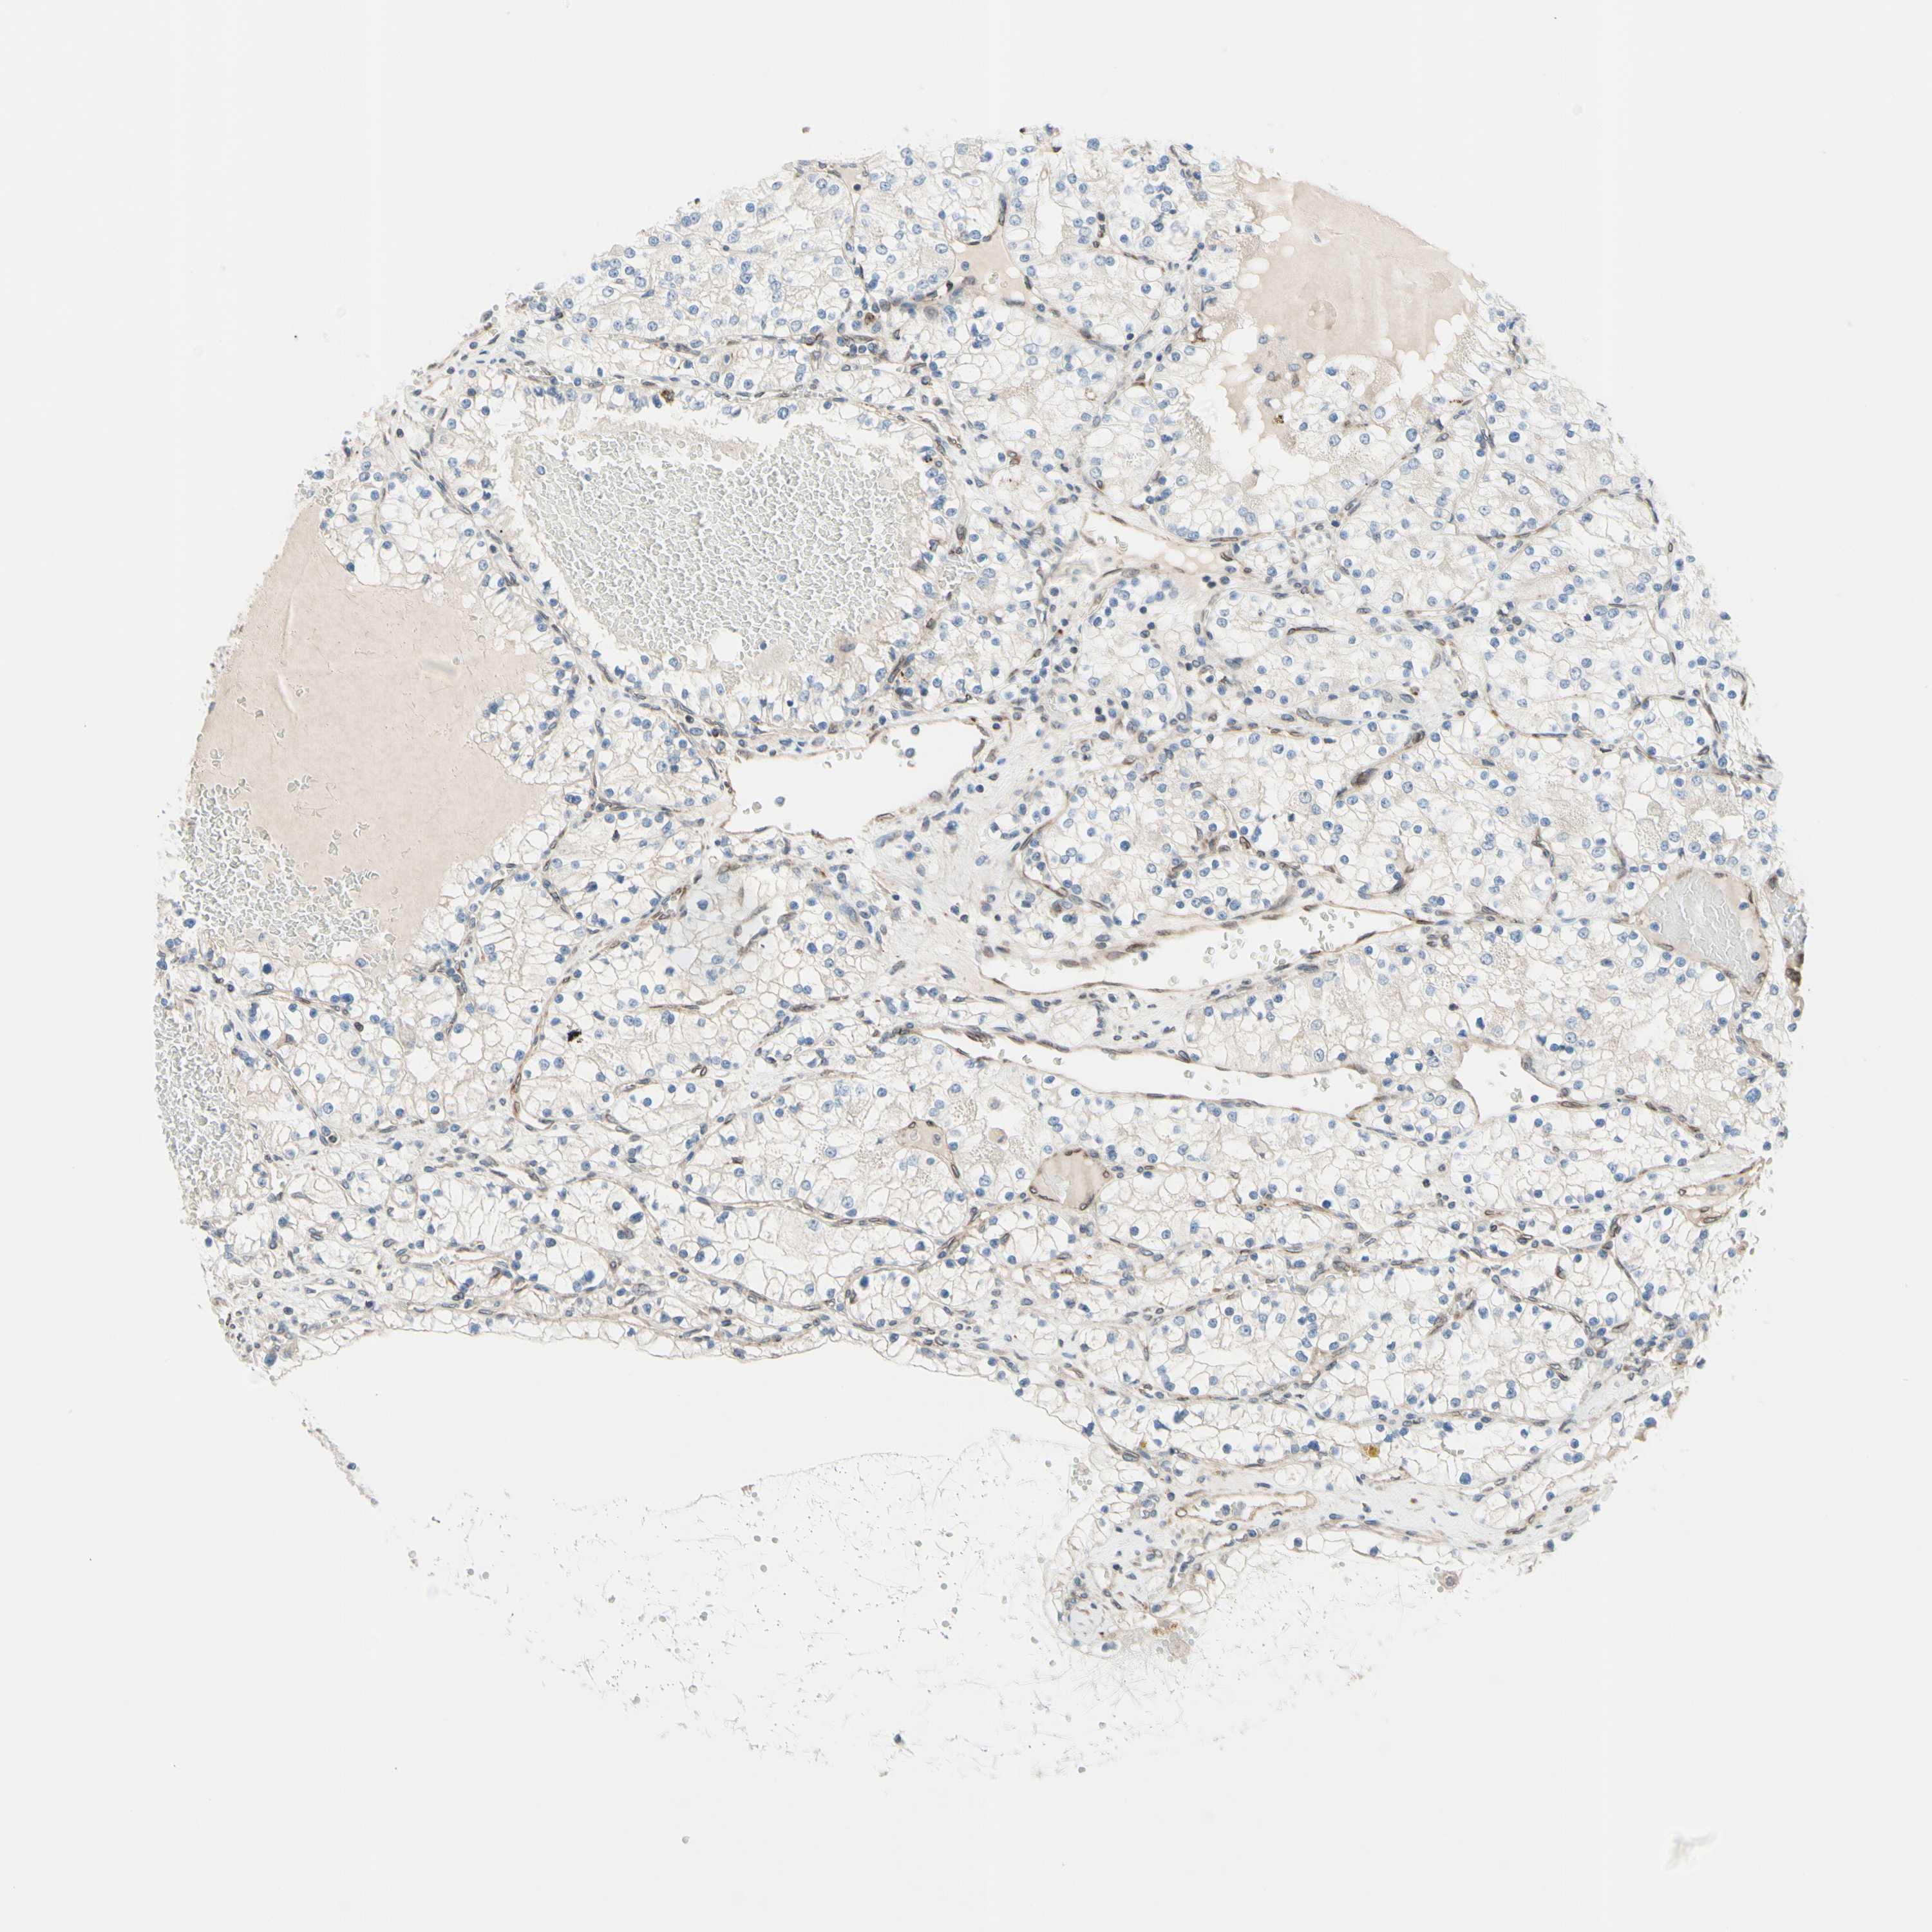

CANCER RENAL CANCER Show tissue menu

KICH TCGA KIRC TCGA KIRC VALIDATION KIRP TCGA PROTEIN RCC CPTAC PROTEIN EXPRESSION

Kidney chromophobe